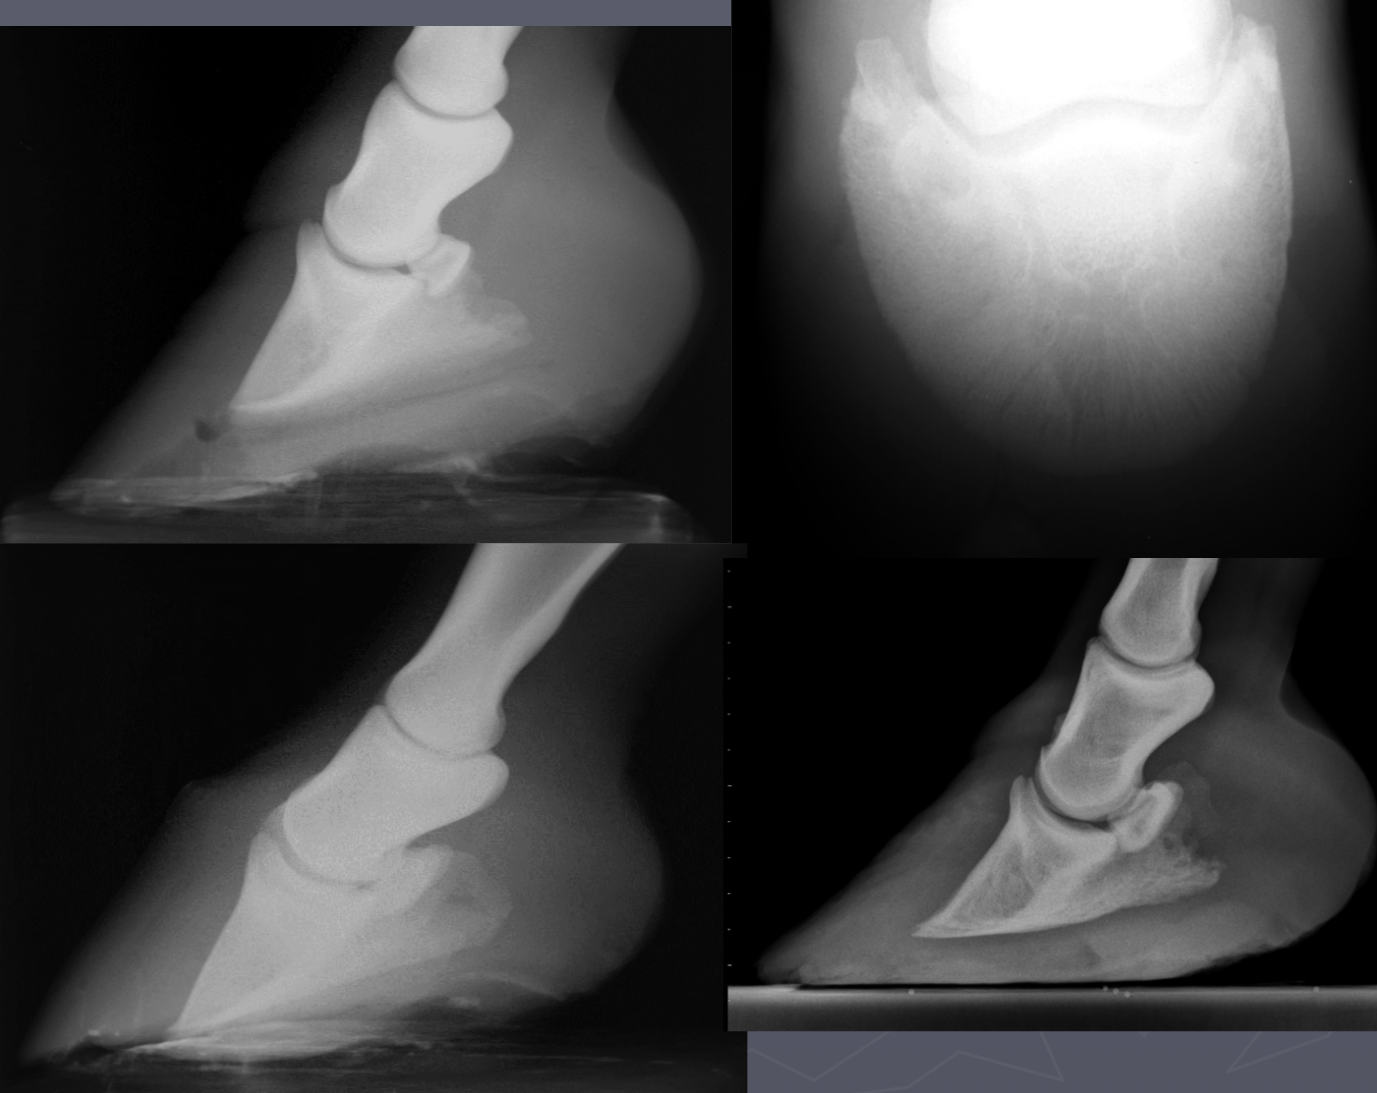

what are 3 measurements for laminitis

palmar displacement of P3 - rotation/tipping

hoof wall: P3 ratio

coronary bad to extensor distance - sinking

laminitis

DJD low ring bone signs

osteophytes P2-P3

NON-AGG lesion

incongruity of joint space on wt bearing rads

low ringbone DJD